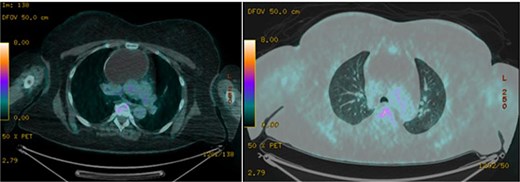

A 51-year-old woman with a history of insulin-dependent type 2 diabetes mellitus and Henoch-Schönlein purpura without history of tobacco or alcohol use presented to the emergency department after being struck by a slow-moving motor vehicle as a pedestrian. On initial evaluation, the patient reported mild shoulder pain but denied any further injuries or symptoms. Workup included a chest X-ray, which demonstrated mediastinal widening suggestive of thoracic aortic ectasia. Non-contrast computed tomography (CT) of the chest revealed a large fluid density in the anterior mediastinum with rim calcification, subtle septations, and some nodularity, measuring 7.1 × 9.2 × 11.2 cm, accompanied by multiple small bilateral pulmonary nodules (Fig. 1). The radiologist was concerned about a possible cystic teratoma. A subsequent positron emission tomography (PET-CT) scan confirmed a photopenic mass in the anterior mediastinum measuring 7.0 × 9.4 cm, with no evidence of regional lymphadenopathy (Fig. 2). The patient remained asymptomatic and elected to undergo surgical resection.

Axial images of PET/CT demonstrating a photopenic mass in the anterior mediastinum measuring 7.0 × 9.4 cm.